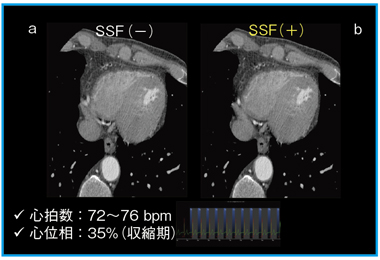

図2は,症例1のアキシャル像だが, SnapShot Freeze(b)により,モーションアーチファクトが大幅に低減されている。

![]() 図2 症例1:アキシャル画像 SnapShot Freeze(b)により,モーションアーチ ファクトが低減されている。 |